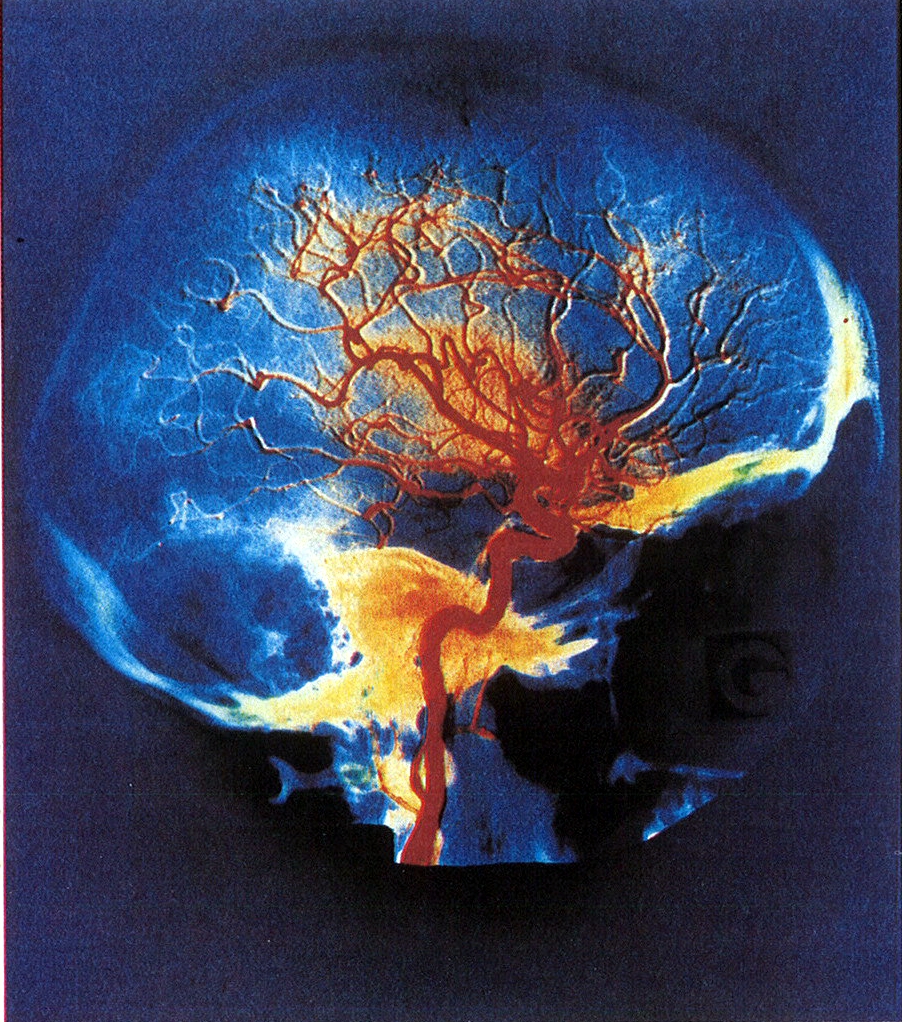

Pour prouver cela, les chercheurs ont utilisé 126 sujets qu’ils ont branchés sur différentes machines, puis leur ont fait passer plusieurs tests concernant les capacités motrices, la mémoire, l’intelligence, y compris un modèle à compléter. Ils analysent ensuite les résultats en observant quelles zones du cerveau ont été le plus stimulées. Une connexion forte entre le lobe frontal et les lobes pariétaux produisent un score d’intelligence fluide particulièrement élevé. Les deux régions en question sont responsables des hautes fonctions neuronales.

De plus il apparaît qu’ont peut à présent, également, faire une sorte d’empreinte digitale des connexions neuronales de chacun, qui sont uniques à chaque individu. Donc grâce à un scanner, les scientifiques pourront nous dire si nous sommes fait pour tel ou tel poste, mais cela soulève pas mal de questions. Tout d’abord, cette étude laisse sous-entendre qu’il y aurait au moins deux catégories de personnes, celles qui sont intelligentes et et celles qui le sont moins. Ainsi, nonobstant nos efforts et notre acquis, ceux qui auraient été déterminés comme moins intelligents seraient forcément plus limités dans la vie.